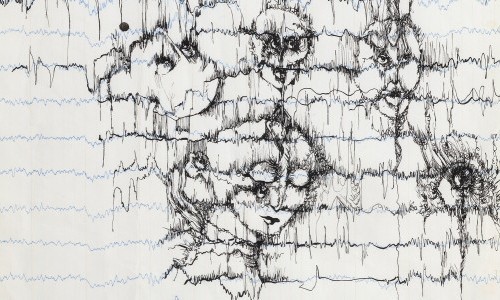

Im Bilderlager der UPK Basel sind auch Arbeiten der Schauspielerin und Zeichnerin Béatrice (Bea) Schweizer (1936–2013) bewahrt. Ihr künstlerisches Werk umfasst rund 600 Bilder, klein- wie grossformatige, und nimmt in der Sammlung der UPK den grössten Umfang ein. Auch formal und inhaltlich handelt es sich um ein eigenwilliges Werk. Es ist vielseitig und zeigt ihr Können. Es liegt nahe, dass Béatrice Schweizer eine künstlerische Ausbildung absolviert haben könnte. Eine Werkgruppe steht im Zentrum der Ausstellung: Zarte Zeichnungen mit schwarzer Tinte auf Registerpapier für EEG-Diagramme. Béatrice Schweizer nutzt den Verlauf der nervösen Kurven der gemessenen elektrischen Aktivität des Gehirns mit ihren unterschiedlichen zackigen Ausschlägen. Sie folgt den Kurven, fährt in rasanten Bewegungen darüber hinaus, verdichtet ihre Striche zu eingeschwärzten Partien, aus denen sich Figuren entwickeln. Beherrscht wird ihr Werk von Motiven des Dämonischen. In den Zeichnungen erscheinen sie wie in das Diagramm eingeschrieben, als würden sie aus den eigenen Hirnströmen herausfliessen und auf dem Papier Gestalt annehmen. Es lässt sich nur mutmassen, mit welchen inneren Dämonen Béatrice Schweizer kämpfte.